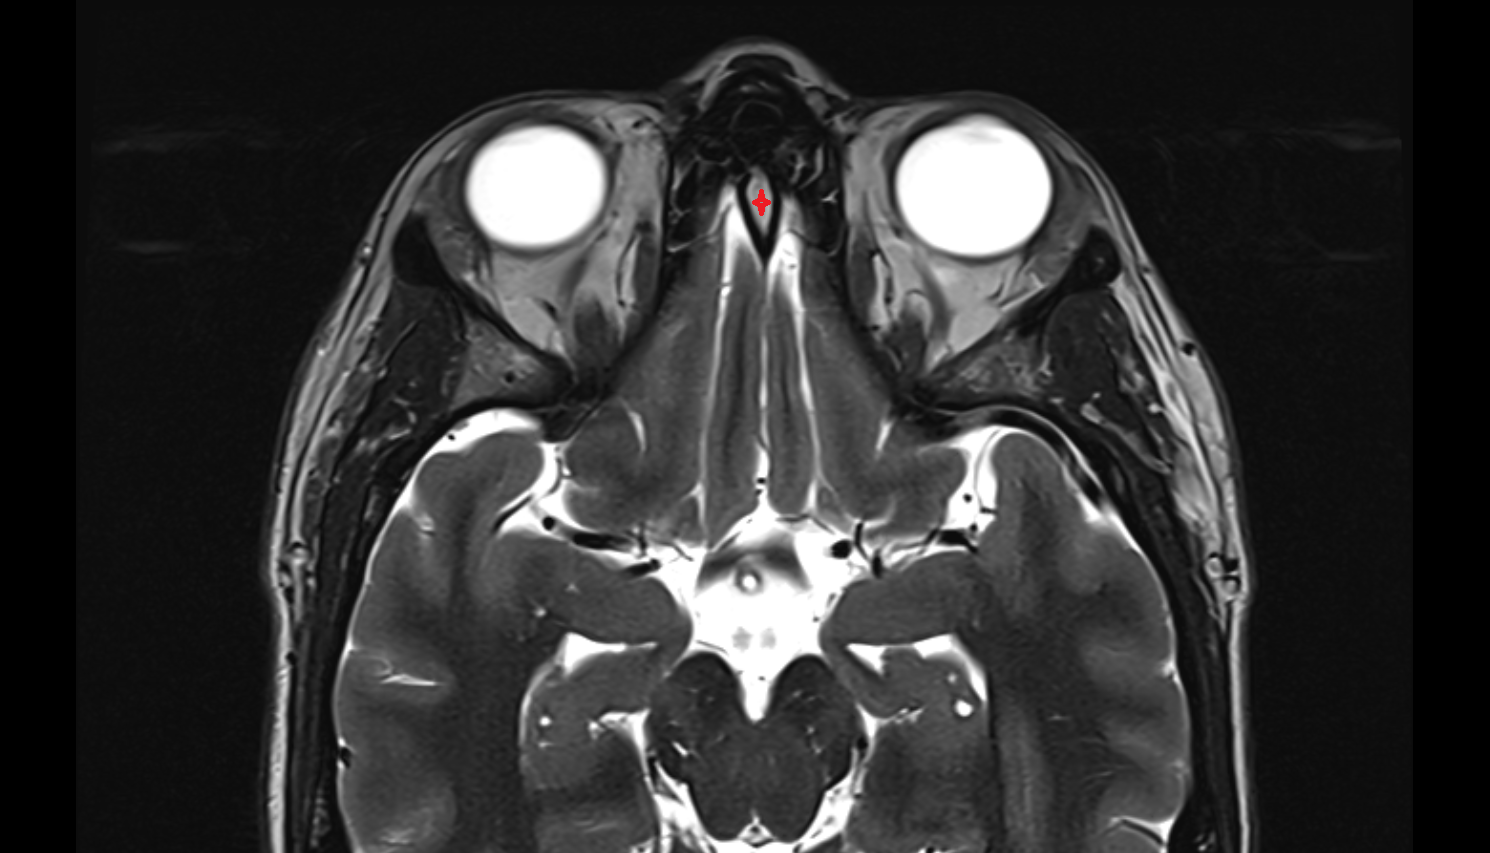

- Optic chiasm

- Optic Nerve (Cranial Nerve II)

- Orbital part of optic nerve

- Optic nerve sheath

- Subarachnoid space of optic nerve